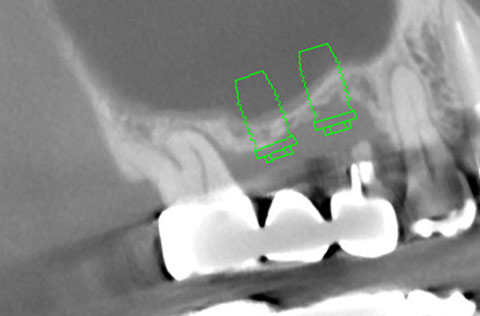

他院でインプラント治療を断られたケース。当院の「ラテラルスリット法」で骨造成を行い、インプラントを埋入できた。